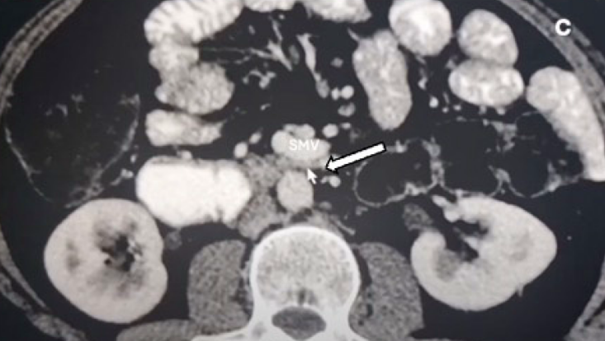

The paper of Shin[3] reports on a quite similar peculiar topographic constellation:

Image from Shin[3] – duodenal compression by the jejunal vein

According to my remarks on the paper from Yetişir [1] these authors describe the compression of the duodenum by the jejunal vein. The similarity to the case of Yetişir [1] is obvious. It would be interesting to know whether the left renal vein was compressed as well, but this was not mentioned in any of the case reports.